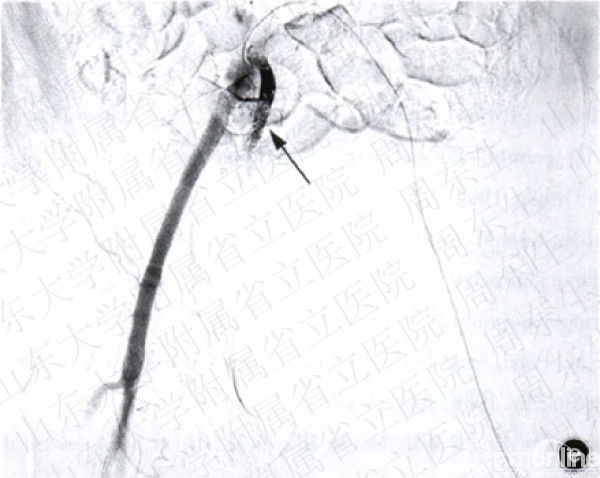

2.栓塞组:局麻后,患者取仰卧位,采用Seldinger法行股动脉穿刺插管(用带芯穿刺针穿透血管,拔出针芯,缓慢向外退针,至血液从针尾喷出,迅速插入导针后,拔出穿刺针,通过导丝引入导管至股动脉)。将5~7F猪尾导管置于腹主动脉分叉上2—3cm,注入对比剂造影,而后更换Cobra导管选择性地行髂内动脉造影,此时可发现动脉出血部位造影剂外渗,形成“冒烟”征(图2a~2c)。选择髂内动脉主干或分支动脉注入明胶海绵颗粒进行栓塞,再次造影复查,如出血征象消失则停止注入栓塞剂(图2d,2e)。栓塞组12例行髂内动脉主干栓塞,1例行骶正中动脉栓塞,4例行髂内动脉分支血管栓塞(闭孔动脉1例,臀上动脉3例)。

图2造影栓塞术止血手术及示意图a骨盆正位x线片示Tile分型A型骨盆骨折b动脉造影示意图示左侧髂内动脉的一个分支出现“冒烟”征,证明有动脉的活动性出血e行髂内动脉造影术示髂内动脉分支出血,典型的“冒烟”症,A为髂总动脉,B髂外动脉,c髂内动脉,箭头示出血点d示意图示注入明胶海绵.等栓塞材料行髂内动脉栓塞,栓塞后再次造影检查示动脉出血征象消失e行墨多髂内动脉栓塞术,再次造影示出血停止,箭头示髂内动脉栓塞部位